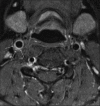

Carotidynia